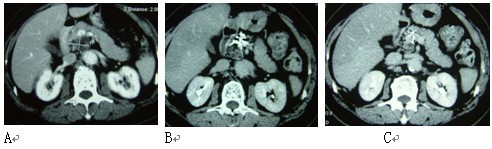

(1)2008年,我们报告49例冷冻加上125碘粒子植入治疗49例局部进展性胰腺癌的结果【14】。49例中,13例接受手术中冷冻,36例接受经皮冷冻。在接受经皮冷冻的患者中,17例接受了第2次冷冻,3例共接受3次冷冻。碘粒子于35例在冷冻的同时植入,14例在冷冻后3-9天植入。术后3个月内作CT评价肿瘤反应,结果显示完全反应(CR)、部分反应(PR)、稳定(SD)和进展(PD)分别为20.4%、38.8%、30.6%和10.2%(图1-5)。中位随访期18个月(5-40月)。中位生存期16.2月。26例(53.1%)生存12个月或更长,其中1例生存54个月,最后死于原发性肺癌。至死胰腺肿瘤未复发(见图1)。36例在随访期死亡,其中17例死于癌播散,11例死于肝转移伴肝衰竭,5例死于心脑疾病。1、2和3年生存率分别为63.1%、22.8%和9.5%。

图1 男性,80岁。胰腺沟突部腺癌。A:治疗前,B:冷冻加碘粒子植入后3个月复查,C:治疗后12个月复查。

患者活存54个月,死于二重癌肺癌。